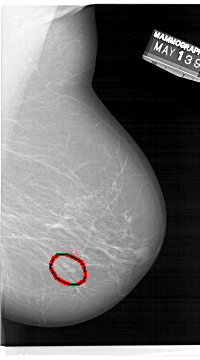

A_1471_1.RIGHT_MLO

RIGHT_CC LINES 6661 PIXELS_PER_LINE 3841 BITS_PER_PIXEL 12 RESOLUTION 43.5 OVERLAY

FILE: A_1471_1.RIGHT_CC.OVERLAY

TOTAL_ABNORMALITIES 1

ABNORMALITY 1

LESION_TYPE MASS SHAPE LOBULATED MARGINS CIRCUMSCRIBED

ASSESSMENT 4

SUBTLETY 4

PATHOLOGY BENIGN

TOTAL_OUTLINES 1

BOUNDARY